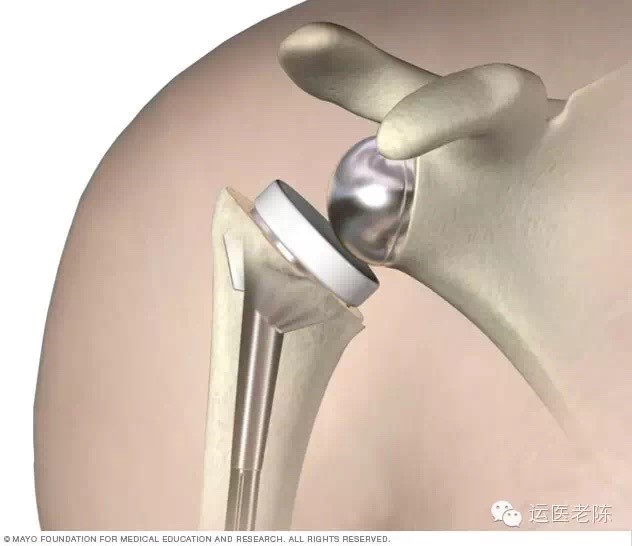

3、关节置换手术

如果我们的肩袖撕裂已不可修复了,同时还存在肩关节的骨关节病,那么可以采用全肩关节置换或反肩置换手术治疗。

图片来源于网络,侵删